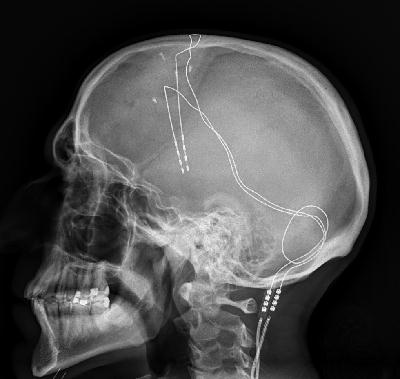

X-ray of deep brain stimulation in OCD

La stimulation cérébrale profonde consiste à stimuler électriquement certaines zones profondes du cerveau au moyen d'impulsions électriques de faible intensité. Elle est notamment utilisée pour le traitement de symptômes moteurs de la maladie de Parkinson. Dans son utilisation clinique actuelle, cette stimulation est délivrée en boucle ouverte (stimulation continuelle à environ 130Hz, 3 à 5 volts d'amplitude). En collaboration avec Prof. S. Palfi et Dr. S. Senova, neurochirurgiens à l'hôpital Henri Mondor de Créteil, nous développons depuis plusieurs années des stratégies de stimulation en boucle fermée qui s'adaptent en temps réel à l'activité cérébrale du patient. L'objectif est une stimulation plus parcimonieuse en vue notamment d'augmenter l'efficacité du traitement, de limiter les effets secondaires et de simplifier le réglage des paramètres de stimulation.